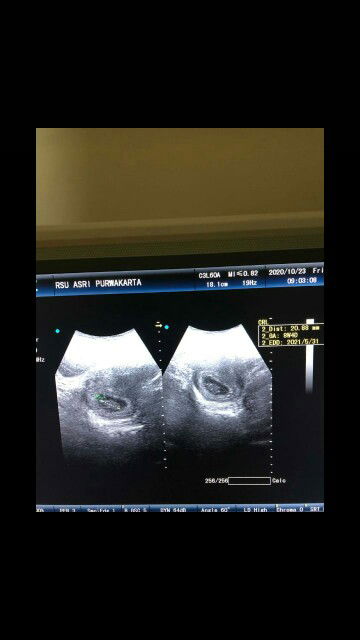

Bun aku hamil 21w kog detak jantung nya udah 150 aja ya bun? Apakah bunda disini ada yg ngalamin sprti sy, ??

Aku 22w tadi di usg detak nya 152 dan gak masalah kok bun. Dokter ku bilang gpp bahkan kalau lg pas aktif gerak bisa nembus 180an masih gpp.. patokan normal itu gak saklek kok.

djj normal 120-160 tapi untuk ukuran tm 2 jika djj lebih dr 160 tdk perlu worry bunda itu tergolong hal wajar. jika tm 3 djj lebih dr 160 itu yg harus pengawasa ketat